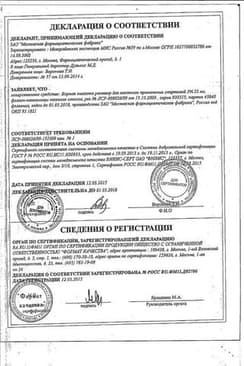

Сертификаты

Сертификаты

7 шт